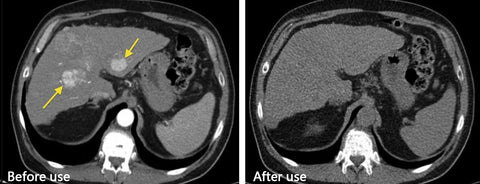

Reducing Inflammation: Prostate problems are frequently linked to inflammation within the prostate gland. The capsules contain a unique blend of natural compounds renowned for their potent anti-inflammatory properties. By targeting and reducing inflammation in the prostate, these capsules help alleviate pain, discomfort, and swelling associated with prostate issues. Interferes with the production or activity of inflammatory mediators, such as cytokines and prostaglandins. By doing so, they help modulate the inflammatory response, resulting in a decrease in inflammation and swelling.

Enhancing Urinary Function: Frequent nighttime urination is a common symptom experienced by individuals with prostate issues. Lancetswell™ Prostate Health Capsules specifically target the smooth muscles and tissues surrounding the prostate and bladder. Through their action, these Capsules relax and strengthen these structures, leading to improved bladder control, reduced urinary urgency, and a healthier urinary flow. This ultimately results in fewer nighttime trips to the bathroom.

Back up by experts and research

A recent Harvard study draws attention to the hard water in the USwhich contains toxic minerals that can create a dangerous buildupinside the body if consumed for a longer period of time